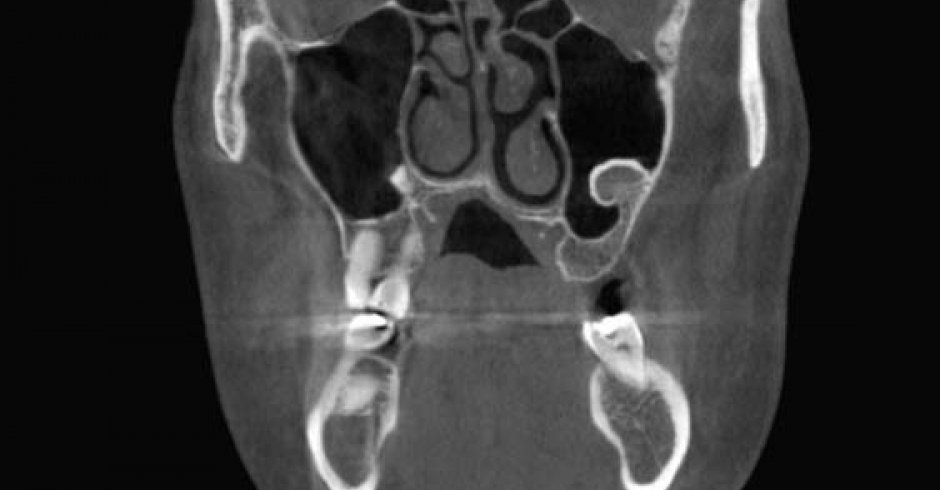

La Tomografía Computarizada Cone Beam (TCCB) es una tecnología en rápido desarrollo que proporciona imágenes de alta resolución espacial del complejo craneofacial en tres dimensiones (3D).